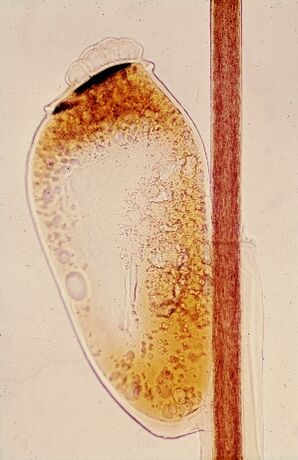

Головна́я вошь[1] (лат. Pediculus humanus capitis) — одна из двух форм, или морфотипов[2] человеческой вши. Среда обитания — волосяной покров головы человека (усы, борода, волосы), откуда и название. Ножки головной вши подходят к обитанию на волосах круглого сечения. На волосах нижней части тела, имеющих треугольное сечение, обитает другой вид — лобковая вошь. От другого морфотипа — платяной (нательной) вши — головная вошь отличается более серым цветом и более коротким туловищем. После поглощения свежей крови цвет тела меняется на красный или пурпурный. Длина взрослого самца 2—3 мм, самки достигают длины 4 мм. Взрослая самка живёт около одного месяца и откладывает пять яиц в сутки. Яйца, или гниды, фиксируются у основания волоса и созревают в течение 7—10 дней. После того, как молодая вошь выйдет из яйца, оно, пустое, остаётся висеть на волосе. Для полового созревания молодой особи требуется около 6—10 дней.